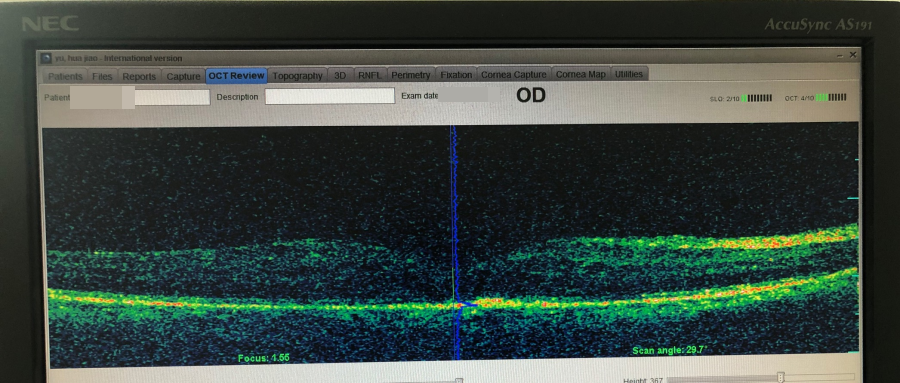

经过OCT光学相干断层扫描及相关检查发现,老人右眼视力仅有0.02,右眼眼底出现黄斑水肿,水肿高度为770μm。

▲微脉冲激光治疗前,黄斑部位明显突出

“医生说,本来这里应该是略微凹进去的,可从片子上看,反而肿得就像个小山包一样!”正是异常的水肿影响了视力。

张伟君说,在黄斑疾病门诊,父亲先后接受了两次微脉冲激光治疗。此后,黄斑水肿高度消退到200μm,效果非常明显!

▲微脉冲激光治疗后,黄斑部位对比明显